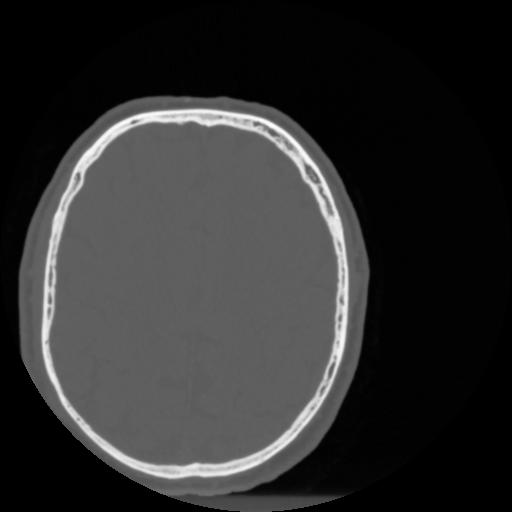

4 CEREBRO,,Vol,0.5,CEREBRO,,